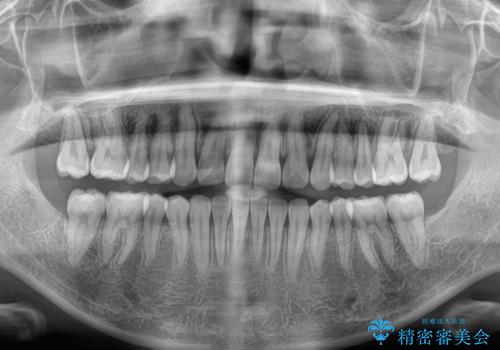

- 上下前歯のデコボコを気にして来院された患者様です。

ワイヤー矯正でもマウスピース矯正でも可能でしたが、短期間で、自身の手を煩わせることなく治療を行いたいとのことで、ワイヤー装置にて矯正治療を行うこととしました。

舌の突出癖により、出っ歯仕上がりとなる可能性がありましたが、舌のトレーニングを頑張っていただき、1年強で終えることができました。